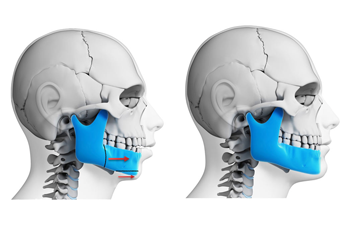

Orthognathic Surgery

Orthognathic surgery is a treatment option in severe bite problems and jaw discrepancies. If you need orthodontic and surgery treatment your orthodontist...

Read More